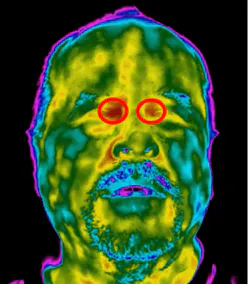

Studies show that the inner canthus (tear duct region) represents the most accurate part of the face when it comes to optical temperature measurement (Figure 2). The inner canthus is only about 5 to 7 mm in size. Using a thermal camera, the inner canthus needs to be covered with enough pixels for an accurate measurement. The projected pixel size for the inner canthus area needs to be around 1.5 mm/pixel or better for best results.